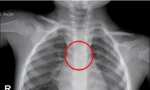

Tại đây, các bác sĩ tiến hành thăm khám, chụp chiếu và phát hiện dị vật hình dạng giống tăm tre đã xuyên thủng thành đại tràng, gây viêm phúc mạc khu trú.

Các bác sĩ sau đó đã tiến hành phẫu thuật lấy dị vật là một chiếc tăm tre dài khoảng 5cm ra khỏi cơ thể bệnh nhân và xử trí tổn thương, lấy mẫu bệnh phẩm làm xét nghiệm giải phẫu bệnh.

Theo bác sĩ Nguyễn Sóng Hồng - Trưởng Khoa Ngoại (Trung tâm Y tế Anh Sơn) cho biết, trong quá trình mổ, các bác sĩ phát hiện đầu tăm dài đâm xuyên thành đại tràng, gây tổn thương nghiêm trọng. Kíp phẫu thuật đã tiến hành lấy dị vật, làm sạch ổ bụng, khâu phục hồi tổn thương. Sau phẫu thuật, bệnh nhân được theo dõi tích cực và hiện tình trạng ổn định, phục hồi tốt.